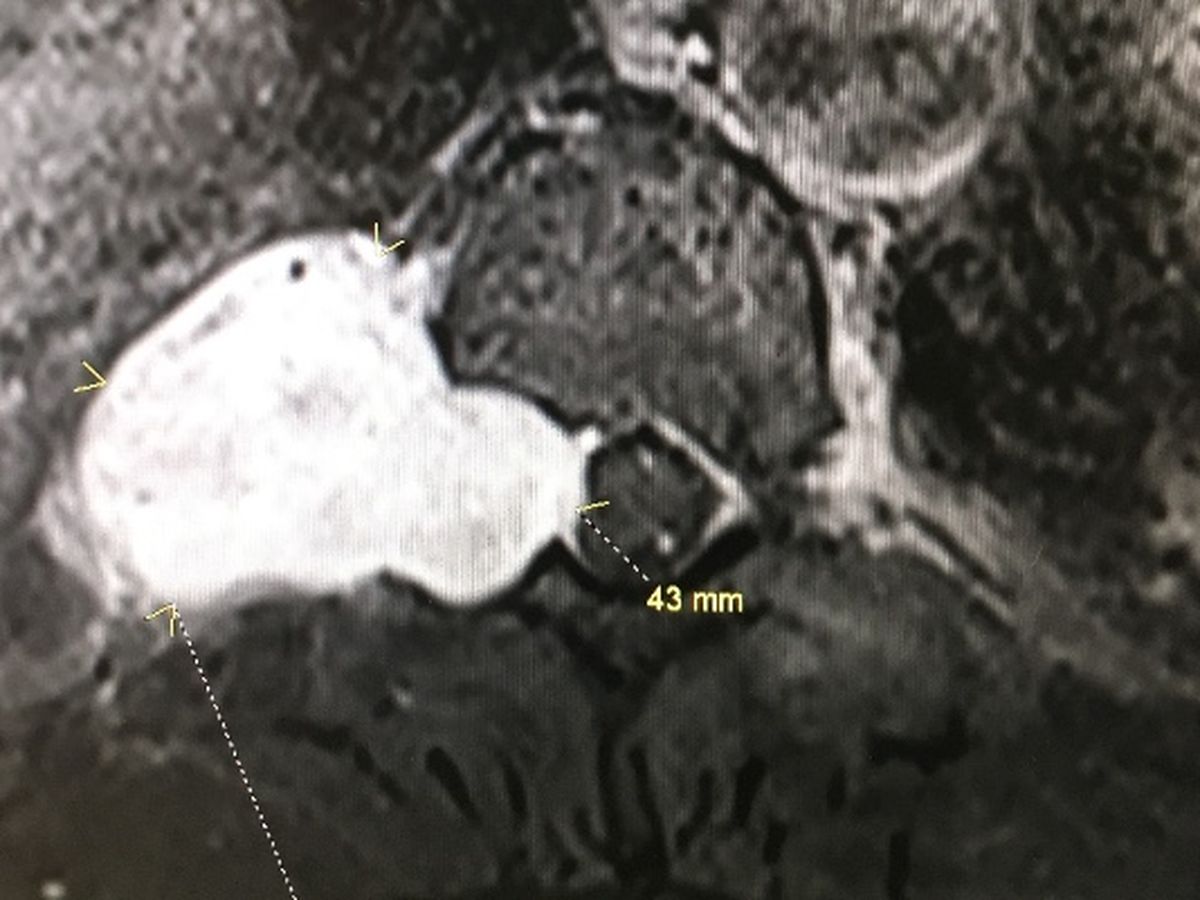

I have a tumor that is on my spine that is deteriorating my spine and wrapped around my nerve endings. The way the tumor is the Drs don't know if they can fully get the whole thing out, there is a chance that I might be paralized if something goes wrong so basically the Dr had to completely take out my T-7 through my T-11 fuse them together and replace them with rods and screws. Since it's wrapped around my spinal cord and has consumed my nerve endings were probably going to be doing radiation or chemo therapy afterwards and I'm gonna have intense physical therapy for the next 6 to 8 months.I didn't want to tell everyone this way but this is the only way i know how to try and get help with all the medical bills and treatment sessions that I'm going to be going